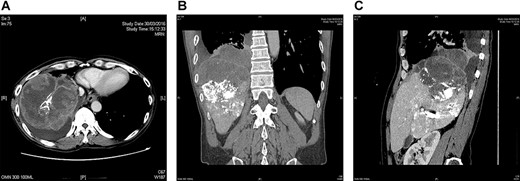

A repeat CT after TACE and PVE though showed sufficient hypertrophy of left liver, it also revealed significant growth of tumor with invasion to right lower lobe of lung through diaphragm (Fig. 1). Operation proceeded with a Mercedes-Benz incision with patient placed in supine position. Tumor was found to invade through medial part of diaphragm to right lower lobe of lung for 3 cm depth. Anterior approach right hepatectomy was performed [4]. Diaphragm was divided surrounding the tumor invasion site. En bloc wedge resection of the involved right lower lobe of lung was performed with endovascular staplers via the diaphragmatic opening. The diaphragmatic defect was closed with Goretex mesh (Fig. 2). Patient made an uneventful recovery and went home on Day 8 after surgery. Pathology confirmed a 12.5 cm poorly differentiated HCC invading through diaphragm to lung (Figs 3 and 4). Both resection margins at liver and lung were >1 cm. AFP decreased to 3 μg/l after operation.

CT showing a large hepatocellular carcinoma invading through diaphragm into lung base. (A) axial view, (B) coronal view and (C) sagittal view. Hyperdense material within liver is lipiodol deposits after previous TACE.